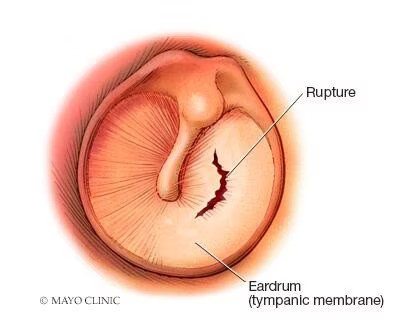

دلایل پارگی پرده گوش : پرده گوش (پرده تمپان) دو نقش اصلی دارد: شنیدن. هنگامی که امواج صوتی به آن برخورد میکنند، پرده گوش به ارتعاش در میآید – اولین مرحله که در آن ساختارهای گوش میانی و داخلی امواج صوتی را به تکانههای عصبی تبدیل میکنند. حفاظت. گوش همچنین به عنوان یک مانع عمل می کند و از گوش میانی در برابر آب، باکتری ها و سایر مواد خارجی محافظت می کند.

اگر پرده گوش پاره شود، مشکلات غیرمعمولی ممکن است رخ دهد، به خصوص اگر بعد از سه تا شش ماه نتواند خود به خود ترمیم شود. عوارض احتمالی عبارتند از:

- از دست دادن شنوایی. معمولاً کم شنوایی موقتی است و فقط تا زمانی که پارگی یا سوراخ پرده گوش بهبود یابد ادامه می یابد. اندازه و محل پارگی می تواند بر میزان کم شنوایی تأثیر بگذارد.

- عفونت گوش میانی (اوتیت میانی). گوش پاره شده ( سوراخ شده ) می تواند به باکتری ها اجازه ورود به گوش را بدهد. اگر پرده گوش سوراخ شده التیام نیابد، تعداد کمی از افراد ممکن است در برابر عفونت های مداوم (مکرر یا مزمن) آسیب پذیر باشند. در این گروه کوچک، تخلیه مزمن و کاهش شنوایی ممکن است رخ دهد.